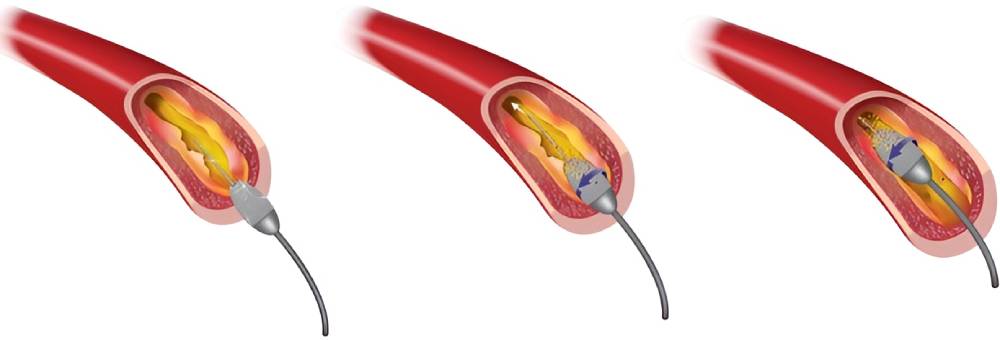

آنژیوپلاستی

اصطلاح «آنژیوپلاستی» به معنای استفاده از بالن برای باز کردن شریان مسدود یا تنگ است. البته در اکثر عملهای آنژیوپلاستی مدرن لولۀ توری سیمی کوتاهی به نام استنت وارد شریان میشود. استنت برای همیشه در شریان باقی میماند تا خون راحتتر جریان پیدا کند.

مراحل انجام آنژیوپلاستی

آنژیوپلاستی قلب با استفاده از بیحسی موضعی انجام میشود، بنابراین بیمار در طول عمل هوشیار است.

متخصص قلب برشی را روی کشالۀ ران، مچ دست یا بازو ایجاد میکند و لولۀ باریک و منعطفی به نام کاتتر را از راه این برش وارد یکی از شریانها میکند. متخصص کاتتر را با توجه به فیلم رادیوگرافی به سمت شریان کرونری درگیر هدایت میکند.

وقتی کاتتر در جای مناسب قرار گرفت، متخصص قلب سیم نازکی را در تمام طول شریان گرفته پایین میبرد و بالن کوچکی را در بخش گرفتۀ شریان قرار میدهد. سپس بالن را باد میکند تا شریان گشاد شود و رسوبات چربی چسبیده به دیوارهی شریان متلاشی شوند. به این ترتیب وقتی متخصص باد بالن را خالی میکند و آن را بیرون میکشد، خون راحتتر جریان پیدا میکند.

اگر از استنت استفاده شود، استنت پیش از جایگذاری دور بالن قرار دارد. وقتی بالن باد میشود، استنت منبسط میشود و پس از خالی کردن باد بالن و بیرون کشیدنش همانجا باقی میماند.

آنژیوپلاستی کرونری معمولاً ۳۰ دقیقه تا دو ساعت طول میکشد. اگر آنژیوپلاستی برای درمان آنژین انجام شود، معمولاً همان روز چند ساعت بعد یا فردای روز عمل مرخص میشوید. بلند کردن بارهای سنگین، فعالیتهای بدنی شدید و رانندگی به مدت حداقل یک هفته ممنوع است.

گاهی اوقات آنژیوپلاستی با لیزر انجام میشود. در این حالت سر کاتتر مجهز به لیزری است که شریان مسدود را باز میکند. متخصص کاتتر ساطعکنندۀ لیزر را در آنژیوپلاستی لیزری وارد بخش گرفتۀ شریان میکند. سپس لیزر را روشن میکند تا لیزر پلاک را تبخیر کند و در نتیجه گرفتگی شریان کمتر شود.

مطالعۀ منتشرشده در سال ۲۰۲۱ حکایت از آن دارد که آنژیوپلاستی با لیزر احتمال بروز عوارض را افزایش میدهد و به همین دلیل کمتر انجام میشود. آنژیوپلاستی با لیزر غالباً برای درمان انسداد مجدد کاربرد دارد؛ در این حالت گرفتگی شریانها پس از انجام آنژیوپلاستی معمول با استنت عود میکند.